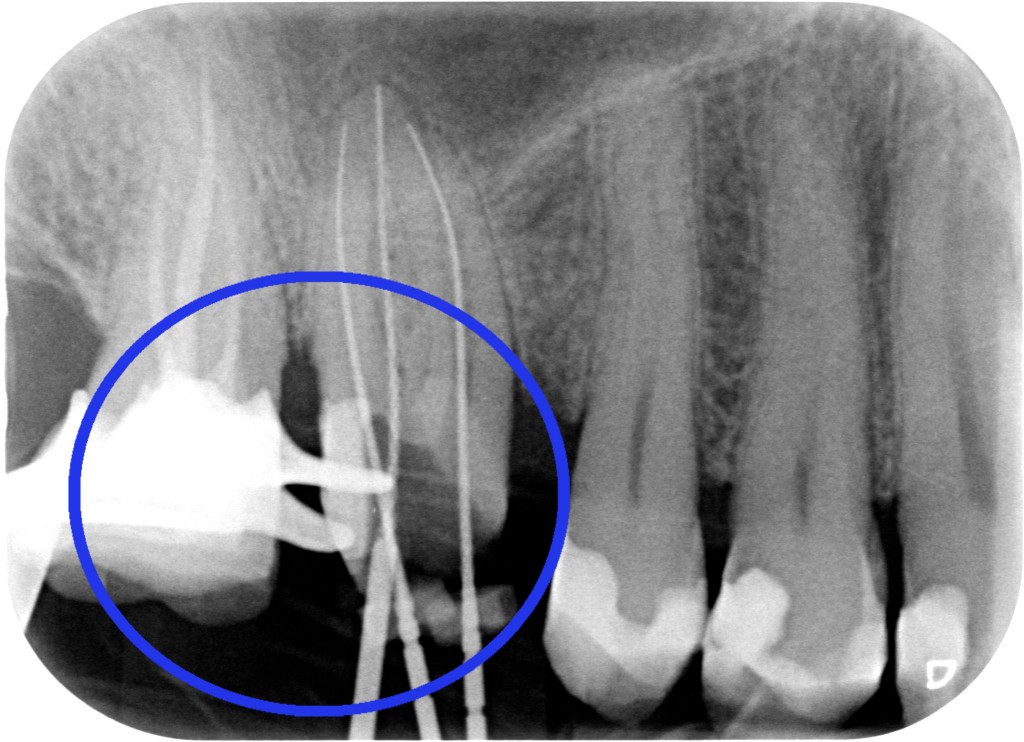

Eseguire un allungamento di corona clinica che richiede TRENTA MINUTI SCARSI(!!!) e restaurare l’elemento con in corretto controllo dei margini protesici.

Il riposizionamento apicale dei tessuti parodontali ci consentirà quindi di:

ESEGUIRE UN CORRETTO PRETRATTAMENTO CORONALE

ESEGUIRE UN CORRETTO RITRATTAMENTO CANALARE ISOLANDO IL CAMPO CON LA DIGA DI GOMMA

ESEGURE UN CORRETTO RESTAURO PROTESICO

“Hei hei guarda un po’ lì cosa ha combinato questo?! Una tacca sul dente dietro!!”

Beh caro amico, la fresa tra i due denti ci deve passare e se le due radici sono troppo vicine bisogna creare lo spazio per una papilla interdentale sana e non sofferente, dove poter mettere un filo retrattore (anzi due) alla presa dell’impronta. Quindi sì, lo ammetto: una tacca di qua e una tacca di là!